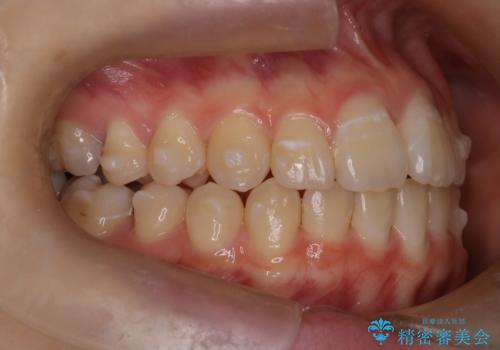

マウスピース矯正で前歯のガタツキを改善! 短期間で治療完了

- 前歯のガタツキが気になるとのことで来院されました。

前歯のガタツキに加え、奥歯の噛み合わせにも問題があったため、マウスピース矯正で治療し改善しました。